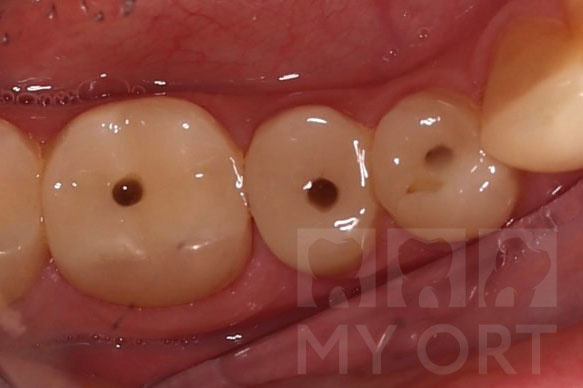

На следующем этапе три зуба были обработаны под постоянные безметалловые коронки из диоксида циркония. Коронки прилегают к зубам максимально плотно, не позволяя развиваться кариесу под ней.

Три зуба обработаны под постоянные коронки из диоксида циркония